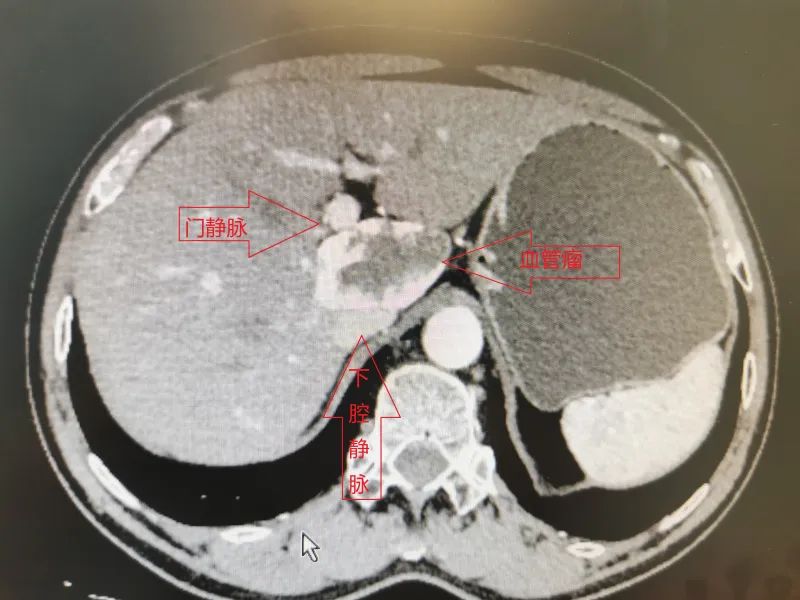

患者术前CT

“大的肝脏血管瘤是定时炸弹,有自发破裂或外伤破裂风险。”韦邦宁解释说,尾状叶位于肝后下腔静脉的前方,第一肝门的后方,三支肝静脉的下方,夹于三个肝门结构之间,位置深、显露困难,周围毗邻门静脉、下腔静脉等粗大的血管。尽管随着肝脏外科技术水平的不断发展,如今针对尾状叶的成功切除手术已逐渐增多,但此项手术依然存在不小的风险。

根据患者具体情况,韦邦宁组织科室骨干积极讨论手术方案,根据CT及血管成像结果,理清肿瘤周围血管分布、走向,并根据手术可能遇到的各种困难制定手术的各种预案。